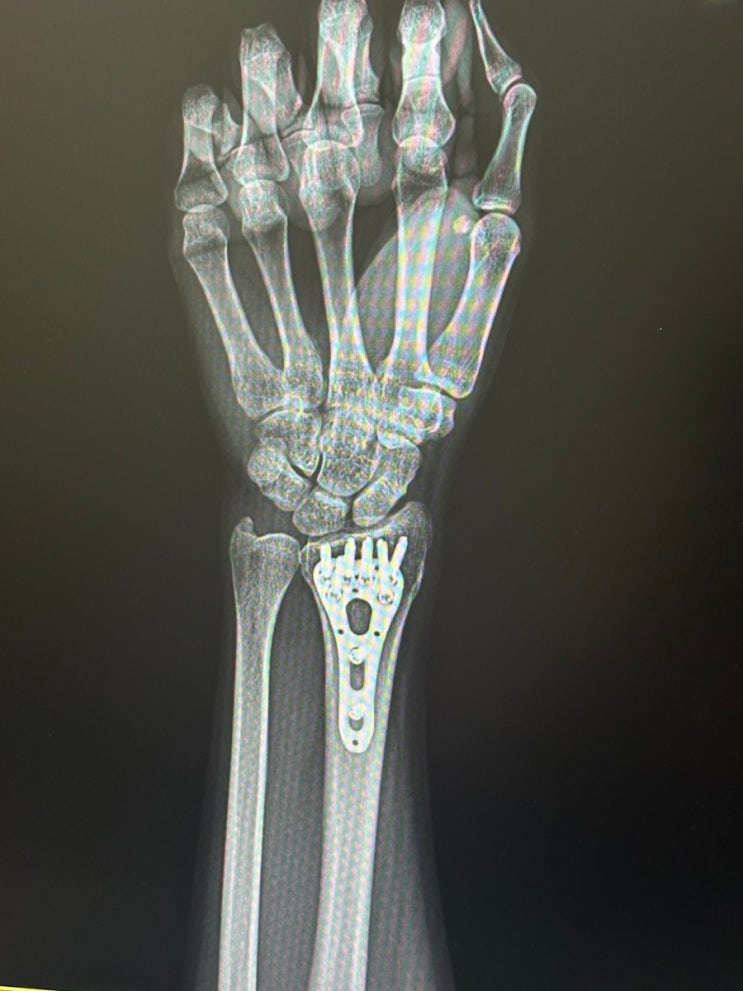

손목 요골골절 핀 제거 수술 후기와 현재 상태

안녕하세요 ! 작년 2월에 요골 골절(distal radial fracture)로 OR/IF 수술받았었고요. 1년 1개월 후에...